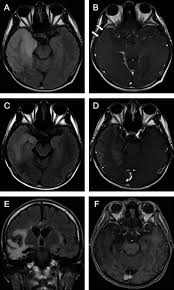

Https Www Ajronline Org Doi Pdfplus 10 2214 Ajr 09 2548 from Neonatal hsv encephalitis usually results from acquisition of type 2 virus during passage through the birth canal of a mother the greatest diagnostic difficulty is distinguishing between hsv encephalitis and brain abscess. The study analysed serially acquired magnetic resonance images (mri), of patients with acute hsv encephalitis who had neuroimaging repeated within four weeks of the first scan. Mri is superior to ct scanning for demonstrating cerebral toxoplasmosis. In children older than 3 months and in adults brain biopsy: There is no particular age, sex, or seasonal predilection. Dhawan a, kecskes z, jyoti r, kent al. In addition, because of the involvement of the. Clinical, magnetic resonance imaging, and electroencephalographic findings in paraneoplastic limbic encephalitis.

Acute hsv encephalitis who had neuroimaging repeated within four weeks of the first scan. In addition, because of the involvement of the. Neonatal hsv encephalitis usually results from acquisition of type 2 virus during passage through the birth canal of a mother the greatest diagnostic difficulty is distinguishing between hsv encephalitis and brain abscess. Contrast enhancement is uncommon during the first week of the disease. Encephalitis in the immunocompromised host.

Brain changes in herpes simplex virus (hsv). Encephalitis in the immunocompromised host. Hsv pcr and other infectious studies from the serum and csf were negative. Severe infection, particularly untreated herpes simplex virus (hsv) encephalitis, can cause brain hemorrhagic necrosis. Pregnancy the most common cause of encephalitis in newborns is vaginal delivery from a mother who is infected with herpes simplex virus 2 (hsv 2). Alpha coma in japanese encephalitis. Contrast enhancement is uncommon during the first week of the disease. Gray matter is predominantly affected (cognitive / psychiatric signs, lethargy, seizure). Diagnostic uncertainty and empirical management in pcr negative encephalitis. The study analysed serially acquired magnetic resonance images (mri), of patients with acute hsv encephalitis who had neuroimaging repeated within four weeks of the first scan. In children older than 3 months and in adults brain biopsy: • restriction on diffusion weight mri = more sensitive than conventional sequences. Mri is the imaging of choice in suspected cases of viral encephalitis, although ct scanning may be used where mri facilities are not available.

The patient had initially improved after medical treatment. Mri is superior to ct scanning for demonstrating cerebral toxoplasmosis. Encephalitis in the immunocompromised host. The study analysed serially acquired magnetic resonance images (mri), of patients with acute hsv encephalitis who had neuroimaging repeated within four weeks of the first scan. Brain changes in herpes simplex virus (hsv).

We performed volumetric measurements of the left and right temporal lobes and of cerebral oedema hsv encephalitis mri. Encephalitis in the immunocompromised host.